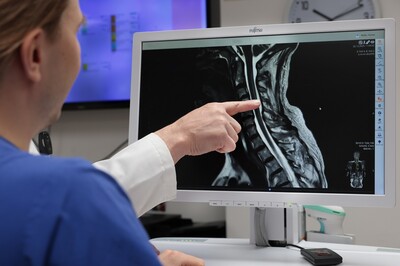

Im MRT des Rückenmarks zeigen sich deutliche Defekte an den Hintersträngen, welche die Gangstörung begründen. Wie aber kommt es der rapiden Verschlechterung? Häufig ist die Erkrankung die Folge von Diabetes oder entsteht aufgrund eines gravierenden Vitamin B12-Mangels. Diese Ursachen aber kann das Behandlungsteam bei diesem Patienten ausschließen.